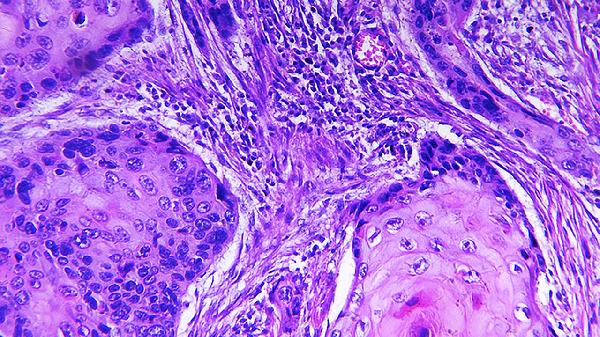

HSV-2则是生殖器疱疹的主要病原体(90%),存在于皮肤和粘膜损害的渗出液、前列腺分泌液、宫颈、阴道分泌液中,主要通过性交传染,引起原发性生殖器疱疹。原发性生殖器疱疹消退后,残存的病毒经周围神经沿神经轴长期潜存于骶神经节,当机体抵抗力降低或某些激发因素如发热、受凉、感染、月经、胃肠功能紊乱、创伤等作用下,可使体内潜伏的病毒激活而复发。人类是疱疹病毒的唯一宿主,离开人体则病毒不能生存,紫外线、乙醚及一般消毒剂均可使之灭活。